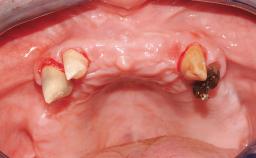

Conventional Loading of Eight Implants in the Maxilla and Final Restoration with a Full-Arch Gold-Ceramic FDP

A 35-year-old Caucasian female presenting with advanced periodontal disease involving both the maxillary and the mandibular dentition was referred for evaluation. The patient, a non-smoker in good general health, requested treatment for recurrent periodontal abscesses, tooth mobility, and discomfort during chewing, as well as restoration of her missing teeth with a fixed prosthesis to improve mastication and esthetics. All residual maxillary teeth exhibited plaque deposits, deep pockets, bleeding on probing, and class III mobility and were evaluated as hopeless. All residual mandibular teeth except tooth 37 could be maintained after periodontal therapy.